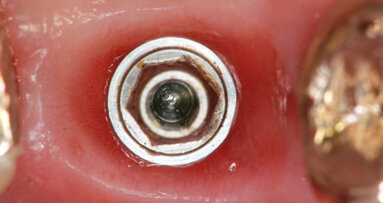

Il nostro obiettivo è quello di riuscire a dare alla paziente un provvisorio immediato nell’arco di due ore. Questo diventa possibile perché abbiamo utilizzato un flusso digitale fin dall’inizio. In laboratorio vengono realizzate la dima chirurgica (Figg. 16, 17), la dima protesica (Fig. 18) e anche il provvisorio (Figg. 19-21) che contiene delle alette di riposizionamento. Il tutto gestito con modelli digitali sui quali saremo in grado di funzionalizzare il provvisorio post-chirurgico (tecnica DIL). In un caso come questo se utilizziamo un flusso digitale possiamo evitare subito dopo la chirurgia di rilevare un’impronta degli impianti inseriti. Infatti, utilizziamo una dima chirurgica che ci faciliterà le fasi di intervento. La dima ci consentirà di non fare lembi e nessuna incisione di rilascio (Fig. 22), dopo aver inserito gli impianti (BLX Straumann) (Figg. 23-31) e aver controllato il loro alloggiamento, inseriamo sugli stessi dei transfert da impronta (Fig. 32).

Fig. 32 - Transfert avvitati sugli impianti.

Alloggiamo la dima protesica (Fig. 33), e blocchiamo i transfert con della resina trasparente (tecnica DIL) (Figg. 34, 35). In questo modo possiamo far riposare il paziente in studio dopo appena 35 minuti dall’inizio dell’intervento. La dima protesica, infatti (Fig. 36) con i transfert inseriti viene completata con l’unione degli analoghi ai transfert (Fig. 37). L’insieme così composto viene riadattato sul modello master digitale iniziale (Figg. 38-40) sul quale era stata costruita sia la dima chirurgica che la dima protesica come anche il provvisorio. Gli analoghi vengono bloccati sul modello con resina trasparente (Figg. 41-43). Alloggiamo il provvisorio sul modello master digitale così ottenuto (Figg. 44, 45).

Le fasi successive sono tecniche, uniamo la componente secondaria angolata a 17° programmata agli analoghi degli impianti (Figg. 46-49), su di essa avviteremo il moncone SRA (Figg. 50, 51). Alloggeremo il provvisorio sul modello (Fig. 52) e le alette di riposizionamento ci consentiranno di essere precisi. Unire il provvisorio alle componenti secondarie sarà a questo punto molto semplice con resina fotopolimerizzabile (Fig. 53). In poco più di un’ora abbiamo funzionalizzato il provvisorio (Figg. 54-57). Il montaggio del provvisorio avverrà collegando prima le componenti secondarie angolate agli impianti (Figg. 58, 59) e poi il provvisorio stesso (Figg. 60-70).

Fig. 58 - Alloggiamento SRA sul 1.2.

Fig. 59 - Alloggiamento SRA sul 2.2.